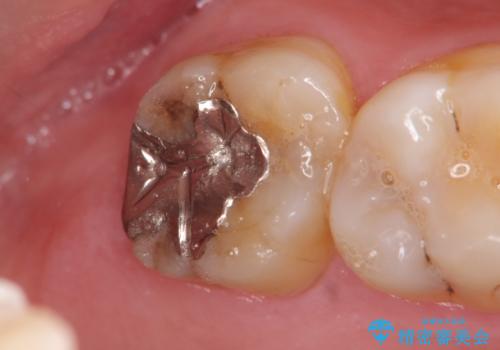

銀歯の劣化・セラミックインレー修復

- 以前に治療を行った銀歯がしみることの改善を希望して来院されました。

銀歯辺縁からのセメント漏洩が認められたため、セラミックインレーによる精度の高い修復を行うこととなりました。

辺縁の漏洩について

修復物の精度が悪いと、接着材であるセメントが漏出し痛みが生じることがあります。